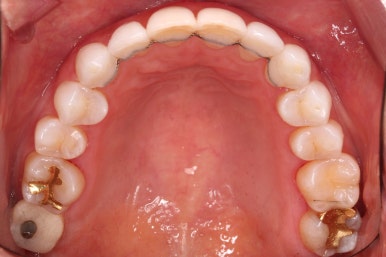

적절하게 치간삭제를 일부 동반하여 빠른 시일 내에 가지런하게 해드리고 마무리를 했습니다.

연산동부분교정 치료 기간이 3개월 밖에 되지 않아 중간 자료사진이 없네요.

환자분이 원하시는 만큼 가지런해졌고, 부가적으로 생길 수 있는 부분들도 수용 가능한 선에서 잘 마무리가 되었습니다.

3개월이라는 빠른 기간 내에(심미보철 보다 약간만 더 긴 시간) 치아의 손상없이 마무리를 잘 했습니다.

아래 앞니는 부분교정까지는 원하지 않으셔서 약간 다듬어 드리고 종료했습니다.